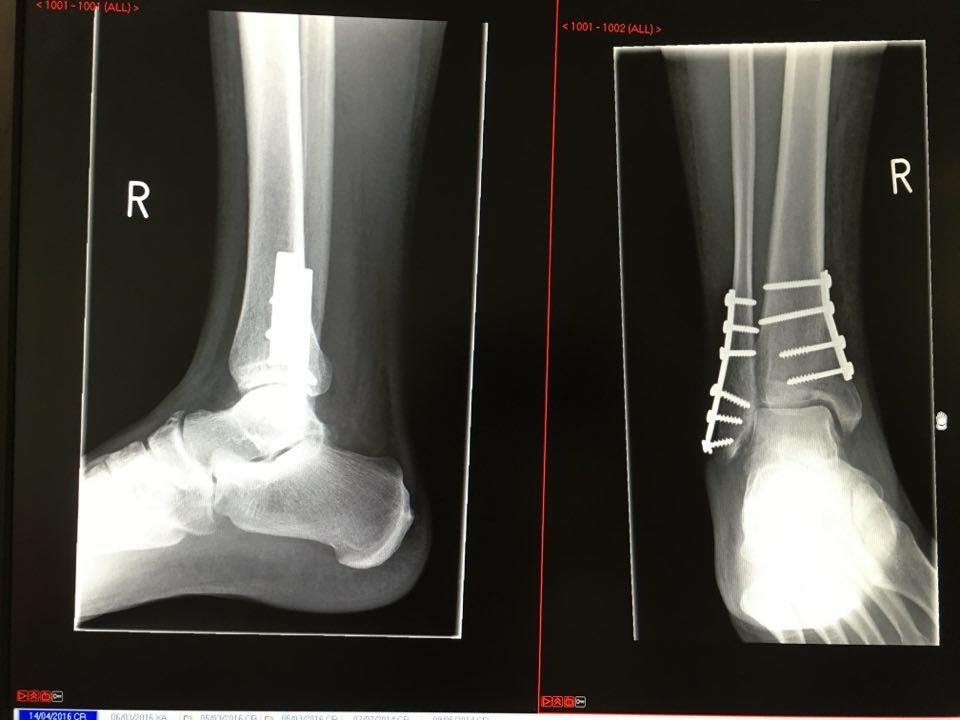

Haha yep that's me, 7 weeks in now. Stepping out of Excavator slipped on mud. Surgeon said I really did a proper job. Never felt anything like it 2 shots of mophine to even touch it at the time

Unfortunately you can't see the full leg x-ray but it was a spiral fracture from just below the knee to the ankle and as wc says, the pain is excruciating. I had to lie on a bed virtually unable to move for two weeks before I went to surgery. There is a picture of the X-fix.